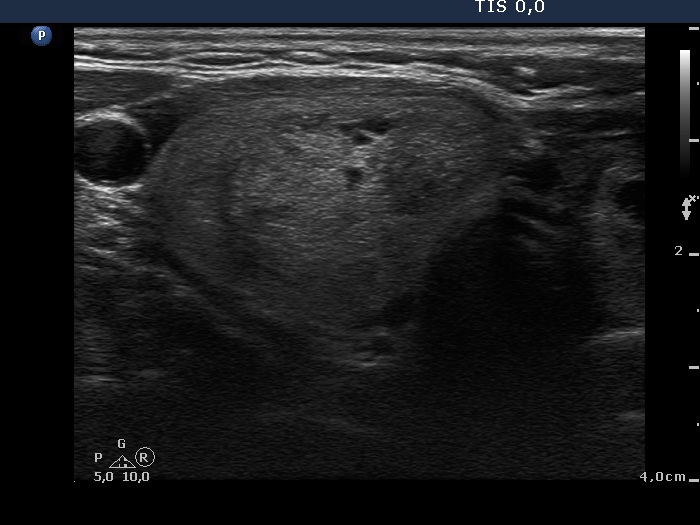

First examination (first row of images):

Clinical presentation: A 57-year-old woman was referred for aspiration cytology of a multinodular goiter has been known for more than two decades. The patient had no complaints.

Palpation: a multinodular goiter without any nodule suspicious on palpation.

Functional state: euthyroidism with TSH 0.96 mIU/L.

Ultrasonography. The thyroid was echonormal and was composed of multiple nodules. Most of them were hyperechogenic or minimally hypoechogenic. There was a hypoechogenic nodule presenting bright hyperechogenic granules in the upper part of the left lobe.

Cytology resulted in benign colloid goiter.